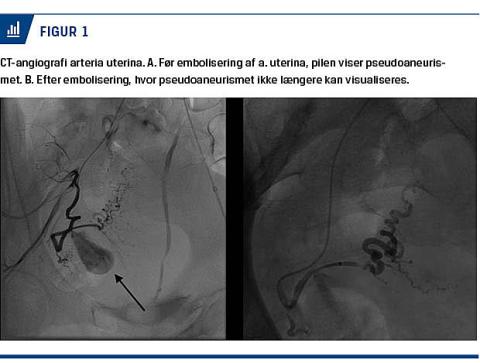

En uge senere blev kvinden genindlagt med fornyet kraftig vaginalblødning. Ved en ultrasonisk undersøgelse fandt man et lille hulrum på 2 × 2 cm med pulserende kar på den cervikokorporale overgang, og der var mistanke om et pseudoaneurisme i højre a. uterina. Diagnosen blev verificeret ved CT-angiografi (Figur 1). Hun blev overflyttet til en billeddiagnostisk afdeling, hvor a. uterina blev emboliseret på begge sider af pseudoaneurismet. Efterfølgende kunne pseudoanurismet ikke længere visualiseres, og blødning samt smerter ophørte.